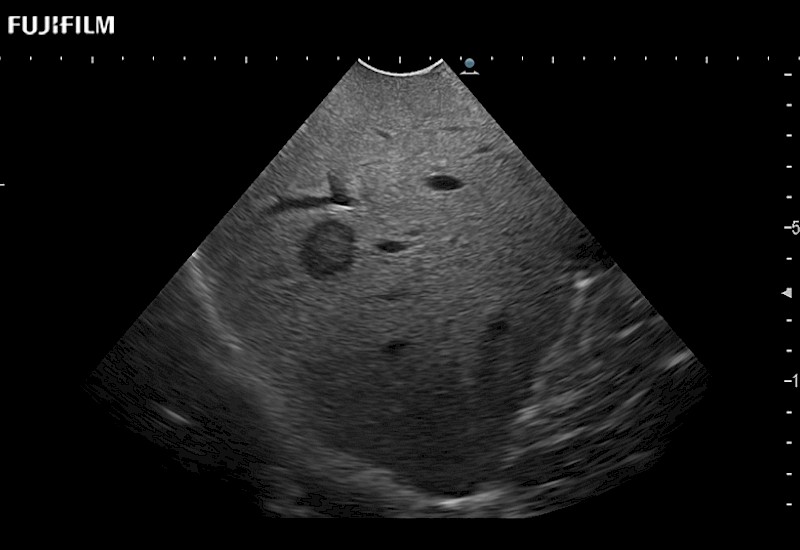

Our dedication to Surgical Oncology allows us to offer superior image quality, outstanding system reliability and intuitive use of cutting edge technology.